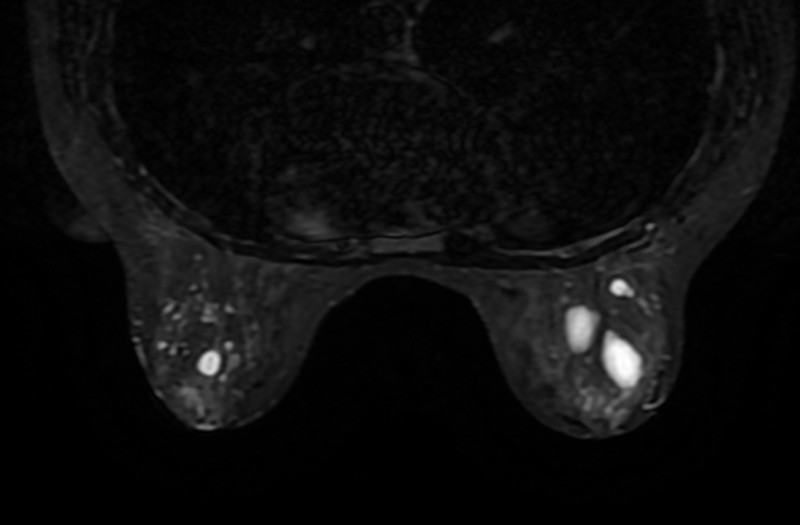

Кисты молочной железы могут быть единичными и множественными, располагаться только в одной молочной железе или же в двух. Размеры кист весьма вариабельны, от небольших до гигантских.

Во время осмотра, при поверхностно расположенных кистах, а также в случае если размер кист превышает 1,5-2 см, то возможно прощупать стенку кисты, определить консистенцию. Обычно это тугоэластической консистенции образования. В положении лежа плотность образования уменьшается. В то же время практически невозможно во время осмотра провести дифференциальную диагностику кисты молочной железы от фибромы или фиброаденомы, поэтому на помощь приходит УЗ диагностика. При УЗ точная диагностика кист молочной железы близка 100%. В сложных и неясных случаях, а также в ситуациях, когда имеется множество кист, проводится рентгеновское исследование (маммография, компьютерная томография).

Осложнения кист молочной железы заключаются в том, что маловероятен, но возможен процесс озлакочествления клеток железы внутри кисты, а также нагноение. В такой ситуации на одной из стенок кисты визуализируется солидное или ворсинчатое образование (в случае рака). Тогда пациентке рекомендуется выполнить тонкоигольную пункцию кисты с забором кистозной жидкости для цитологического и бактериологического исследований.